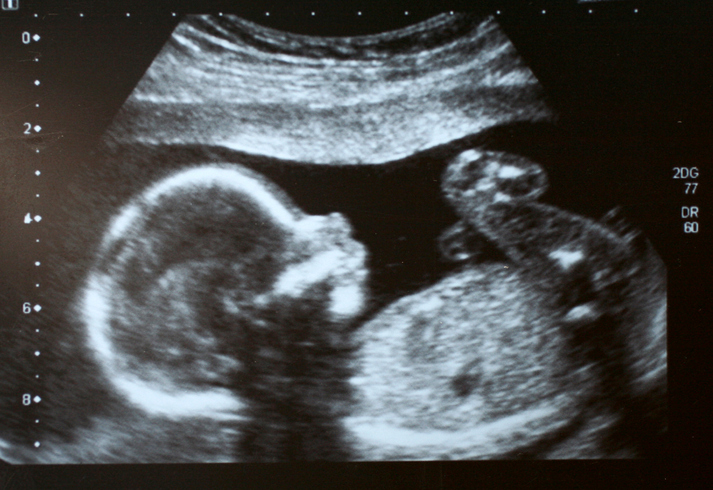

La tecnología y la atención médica prenatal logran reducir las muertes fetales en nuestro país, informó la doctora presidente del colegio de Médicos Ginecobstetra, Alma Delia Arce.

“Estamos a la mano de la tecnología, estamos a la mano de la actualización, por eso es que el esfuerzo de todo el comité y de todo el colegio de Médicos Ginecobstetra del estado de Jalisco, la actualización de las nuevas herramientas con las que contamos para el diagnóstico de cáncer de cuello, para el diagnóstico de cáncer de mama, para el diagnóstico pre natal y el conocer enfermedades de ese nuevo ser, de ese nuevo paciente que todavía no nace”.

Piden a las mujeres embarazadas acudir periódicamente con un médico para reducir las muertes fetales y maternas.